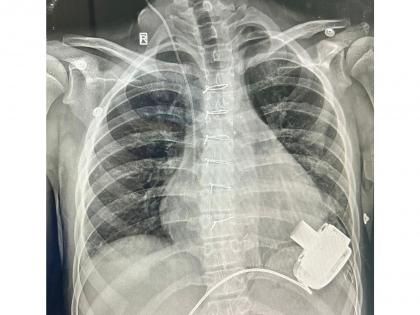

This 14-year-old boy is now the first child to be discharged in northern India after receiving a Mechanical Heart - a Left Ventricular Assist Device (LVAD). He is now also the youngest recipient of an LVAD device in India. This pioneering surgery was performed at the Department of Pediatric Cardiac Surgery at a Private Hospital in Gurugram.

After a complex and difficult surgery that involved connecting a Mechanical Heart Pump to the main pumping chamber of the heart and then connecting the other end (outflow) to the Aorta - the artery that takes blood to various organs of the body. The whole pump is so small that it sits inside the chest and connects to a computerised controller and battery through a small wire that comes out of the skin. As the device was started, it pumped blood from the left ventricle to the body and within a few days in the Pediatric Cardiac ICU, his organ functions started recovering.